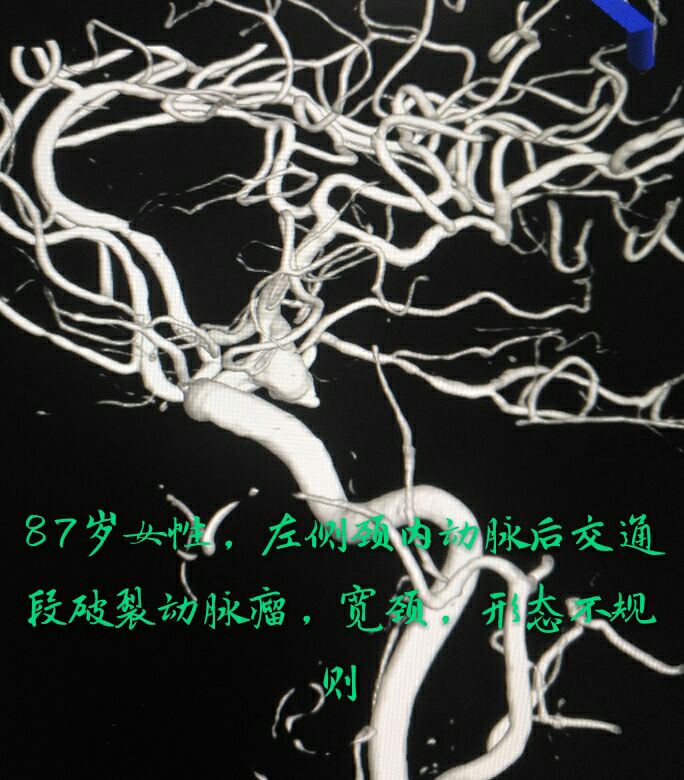

病例三:87岁女性患者,突发头痛、恶心、呕吐,头颅CT示蛛网膜下腔出血量较大,DSA示左侧颈内动脉后交通段动脉瘤,宽颈,形态不规则,有子囊

支架辅助下动脉瘤致密栓塞,因后交通动脉从瘤体发出,并靠近子囊,无法保护,决定牺牲同侧后交通动脉,好在同侧大脑后动脉P1段存在,最终无任何症状体征